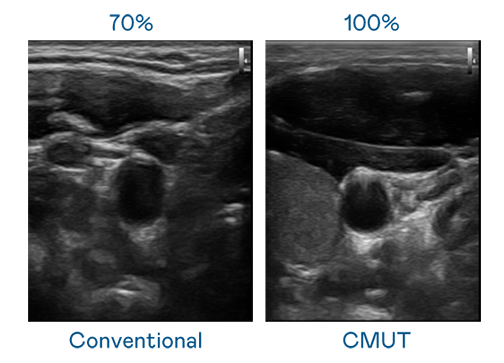

CMUT 技術是一種用電容式微機電元件來產生超音波訊號的技術。與傳統 PZT 壓電式技術相比,CMUT 頻寬增加 30%,更寬頻的超音波訊號讓影像解析度大幅提升,是實現高影像品質醫療超音波掃描、促進精準醫療發展的關鍵技術。

大頻寬帶來超清晰影像

超音波影像的解析度高低,首先取決於探頭能發出的訊號頻寬。G22恒峰 CMUT 可提供高清晰的超音波訊號,提供高頻寬、高靈敏度、影像紋理細節更高的超音波影像,協助醫護人員縮短影像判讀時間及利用精準的醫療影像進行診斷。